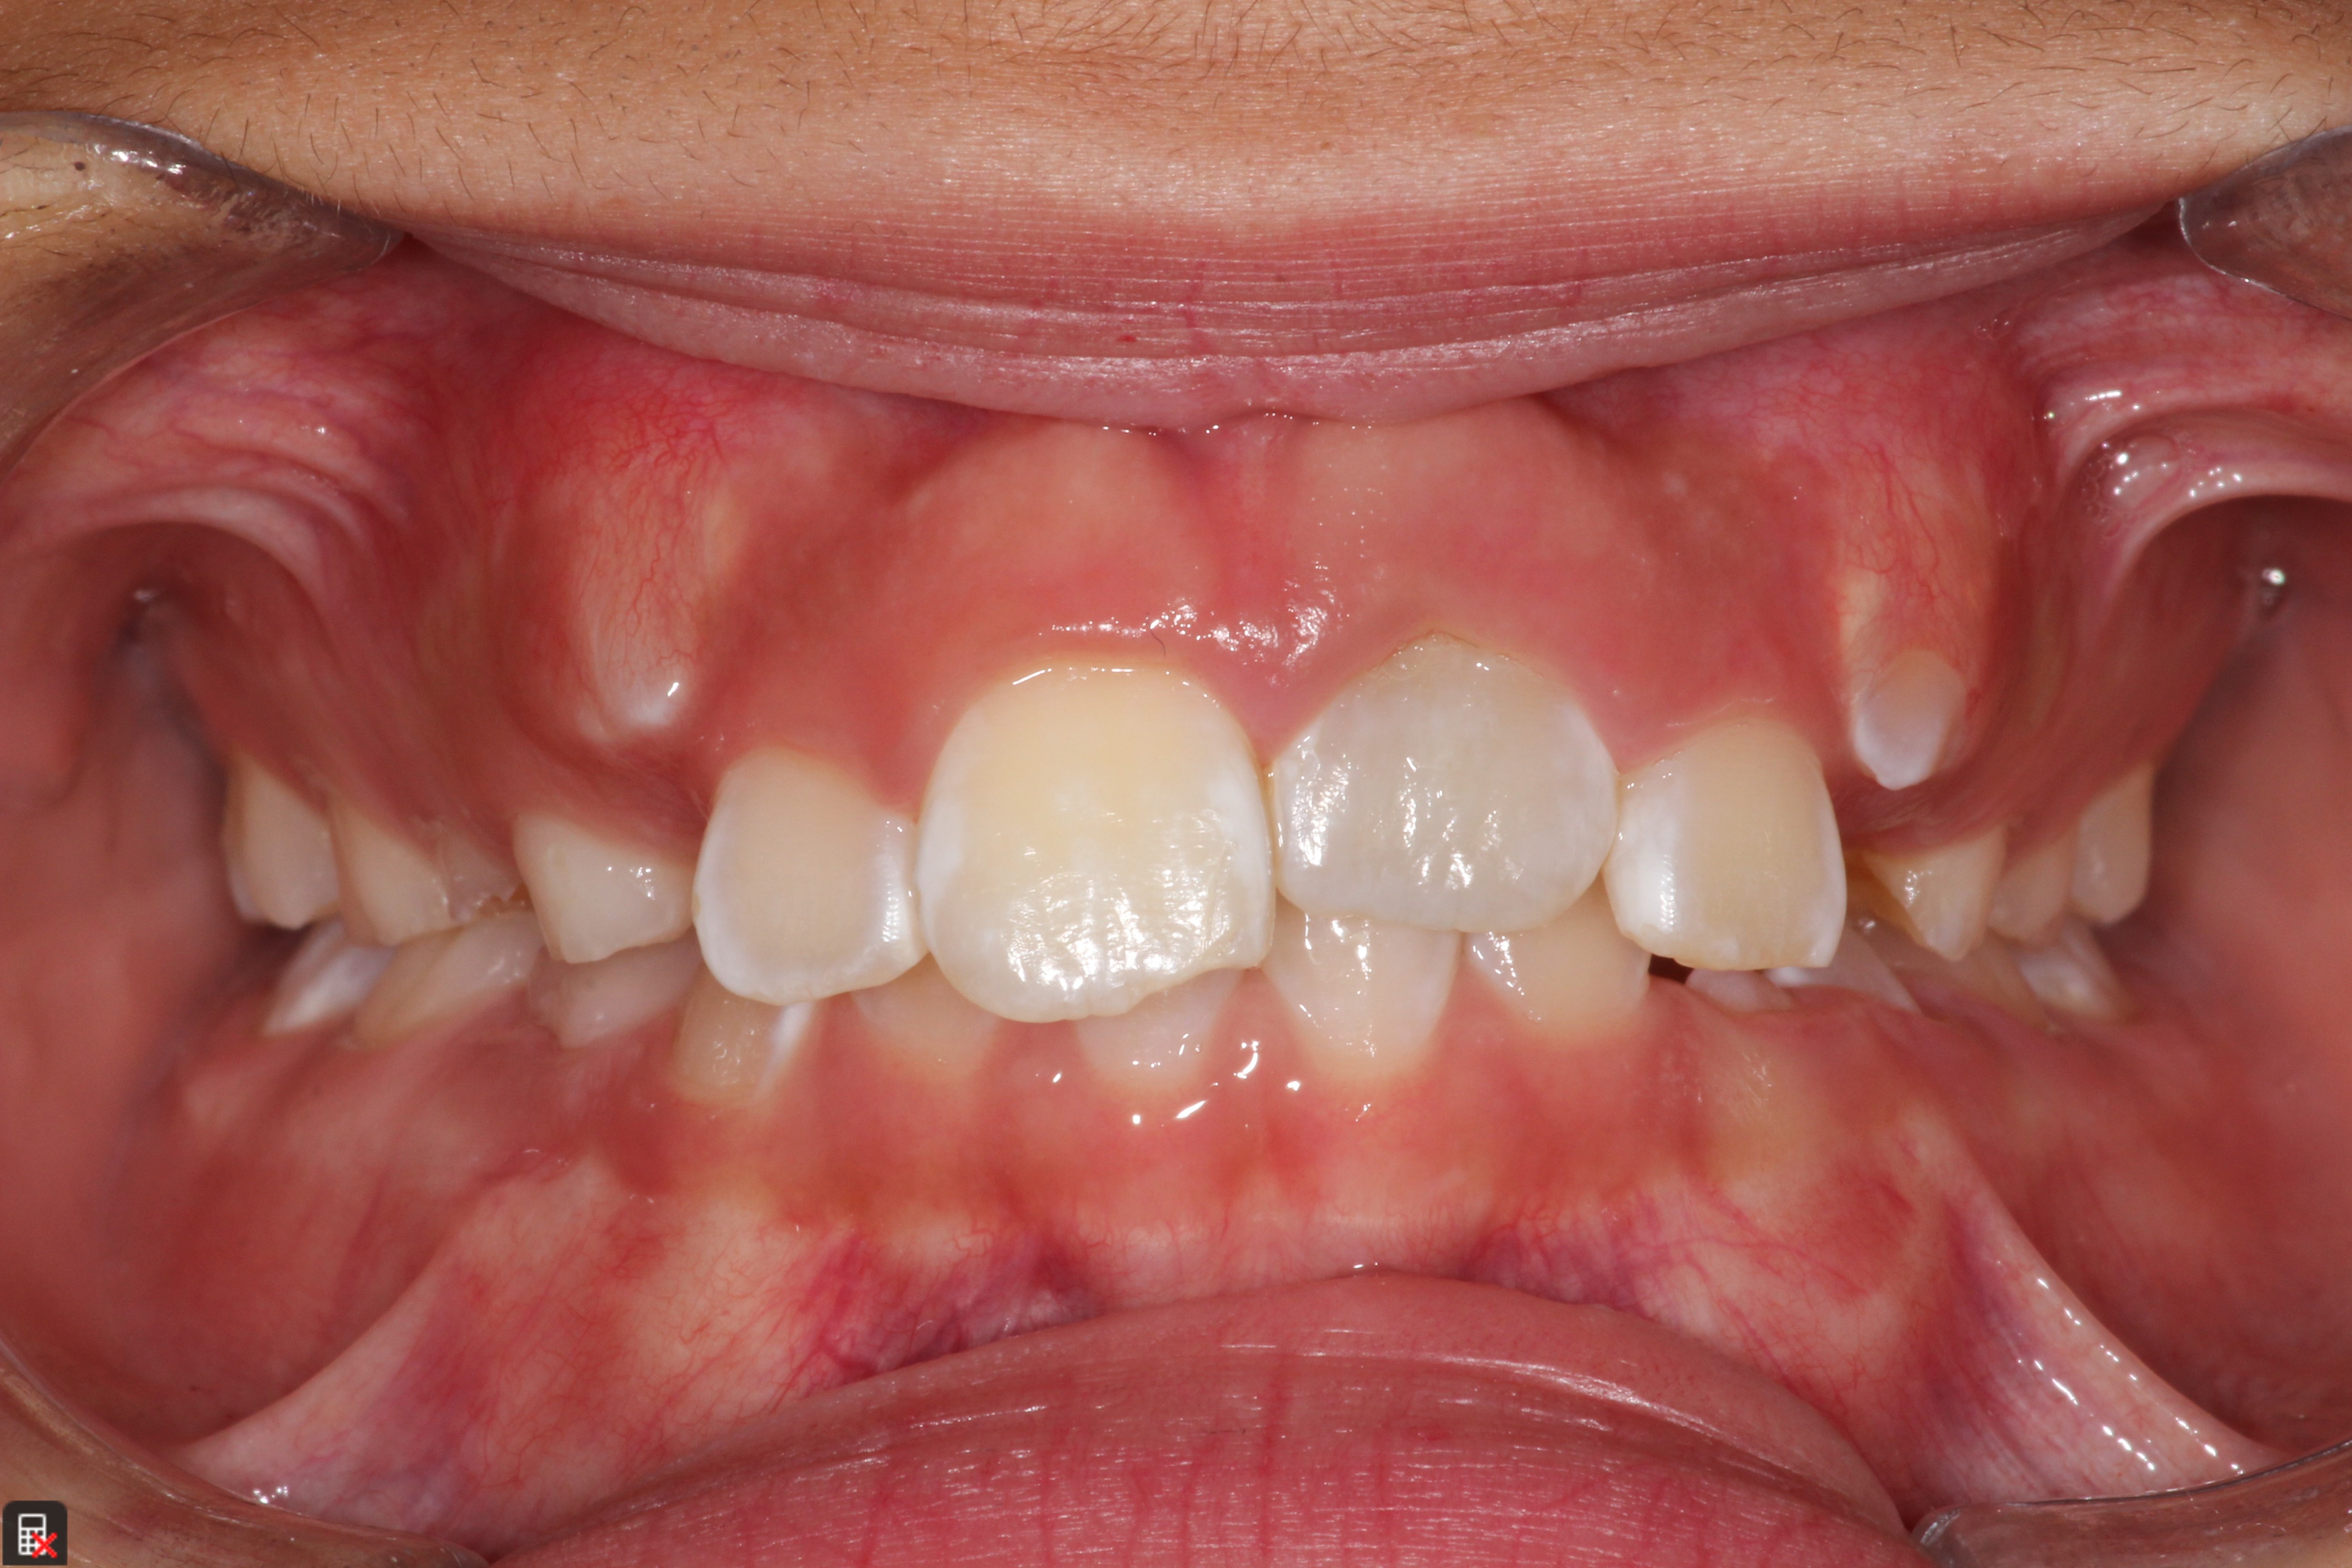

This is a 9yo girl with a high esthetic desire (wants to be a model/actor). She avulsed tooth #9 about 3 years ago, and she has been under treatment with other endodontists. I guess they attempted revascularization with MTA about year ago. #9 is ankylotic with a few mm’s infraposition. It is gray due to the MTA. #8 is slightly yellow/white due to calcification/obliteration but she says she feels cold testing and it is otherwise asymptomatic.

I spoke to her about the following options for #9:

1) Decoronation and a fake tooth for her teenage years

2) No treatment, except internal bleach then bonding/veneer.

3) Autotransplantation of a mandibular premolar

4) Segmental osteotomy/corticotomy later

Are they any other options available? How would you approach this case? Thanks in advance!